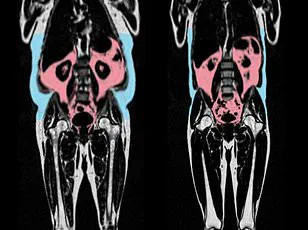

Body shape also emerged as a significant factor in heart health.

Men with an 'apple-shaped' body type, characterized by abdominal fat accumulation, were found to have more rapidly aging hearts compared to 'pear-shaped' women, who tend to store fat around their hips and thighs.

The latter group, known for gluteofemoral fat storage, exhibited healthier cardiovascular profiles.

These findings suggest that where fat is distributed on the body may be more predictive of heart health than total weight alone.